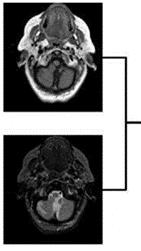

Fig.7.3.1ComputedTomographyScan

Fig.7.3.2Magneticresonanceimaging

Fig.7.3.3FusedImage1

Fig.7.3.4FusedImage2